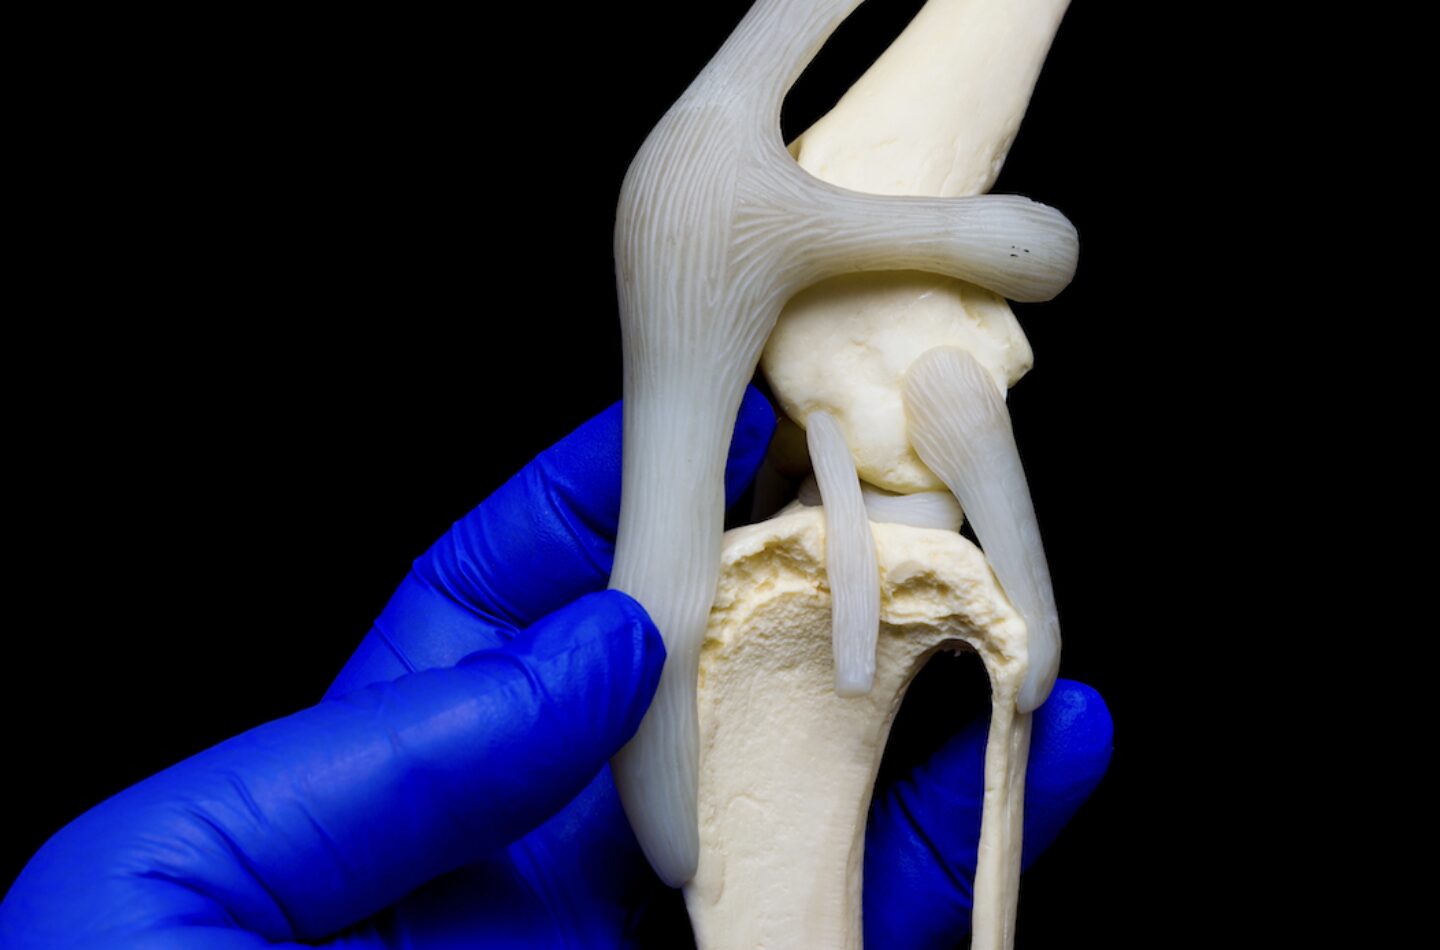

Der Schubladentest. Mit der distal fixierenden Hand kann man die Tibia nach kranial verschieben, wenn eine Ruptur des vorderen Kreuzbandes vorliegt.

Die Schubladenprüfung erfolgt in Seitenlage bei leicht gebeugtem Knie (ca. 120–140°). Der Femur wird über die Kondylen fixiert, die Tibia am Tibiakopf gefasst und kontrolliert nach kranial verlagert. Entscheidend ist nicht nur das Vorliegen einer Translation, sondern deren Qualität: klar begrenzt oder weich-diffus, schmerzhaft oder schmerzfrei. Ergänzend kann der Tibia-Kompressionstest durchgeführt werden. Eine kraniale Tibia-Verschiebung bei Flexion des Tarsalgelenks spricht für eine Insuffizienz des kranialen Kreuzbandes. Der Sitztest kann Hinweise liefern, ist jedoch unspezifisch und allein nicht beweisend.